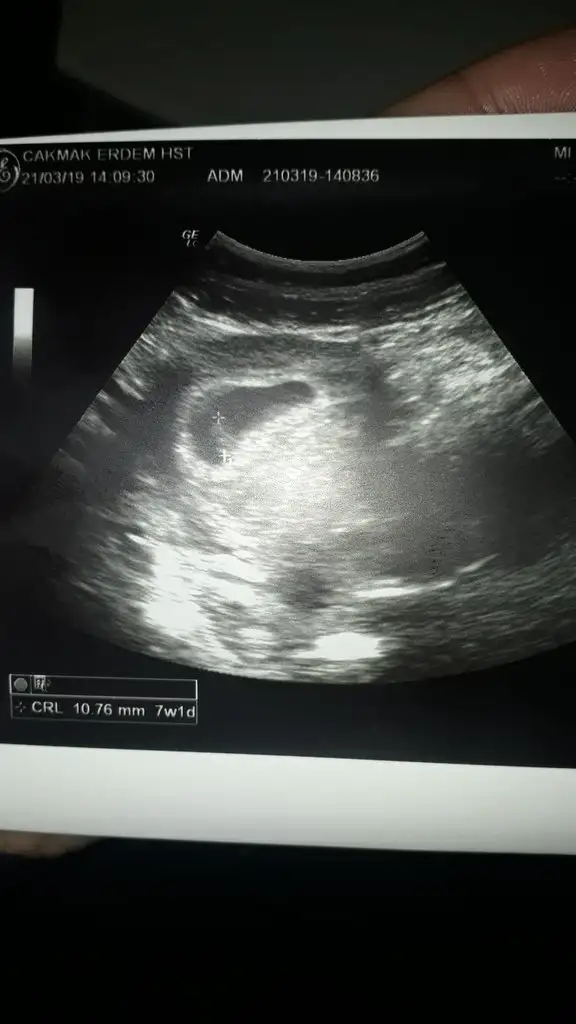

Cok sukur sevindim senin adına kuzum. Ee hani ultrason resmi yok mu 😊

IMG-20190321-WA0006.webp

Bu da fasulye tanem Teyzoşları 🤗🤗